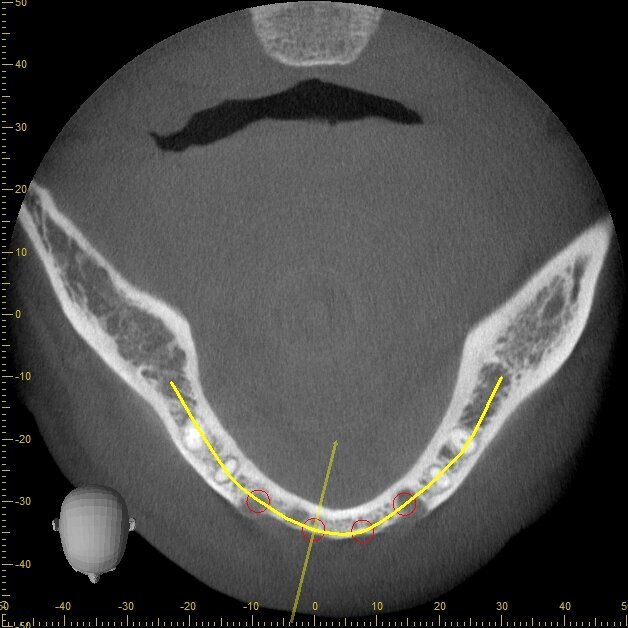

Viene presentato il caso di un paziente (maschio, 57 anni) inquadrato nosologicamente come ASA 1 e riferito alla nostra osservazione per la riabilitazione implantoprotesica di un’area edentula in mandibola anteriore (Fig. 1). Le indagini radiografiche di 1° e 2° livello (ortopantomografia e CBCT) evidenziano una marcata atrofia ossea di tipo combinato (classificabile come grado 3 sec. Seibert) che controindica l’inserimento di impianti osteointegrati (Fig. 2). Considerato il notevole riassorbimento della cresta ossea, per ridurre il rischio di incidenti intraoperatori e poter pianificare al meglio l’intervento chirurgico, viene simulato il posizionamento di 4 impianti Resista IA3413 (Resista, Via F.lli Di Dio, 68 – Omegna, VCO) tramite il software per ricostruzione tridimensionale Real Guide Ver. 5.0 (3Diemme, Como).

Fig. 3 - Esame CBCT preoperatorio che evidenzia l’anatomia ossea residua.

Fig. 4 - Simulazione preimplantare che evidenzia la limitata disponibilità ossea in senso verticale e orizzontale.